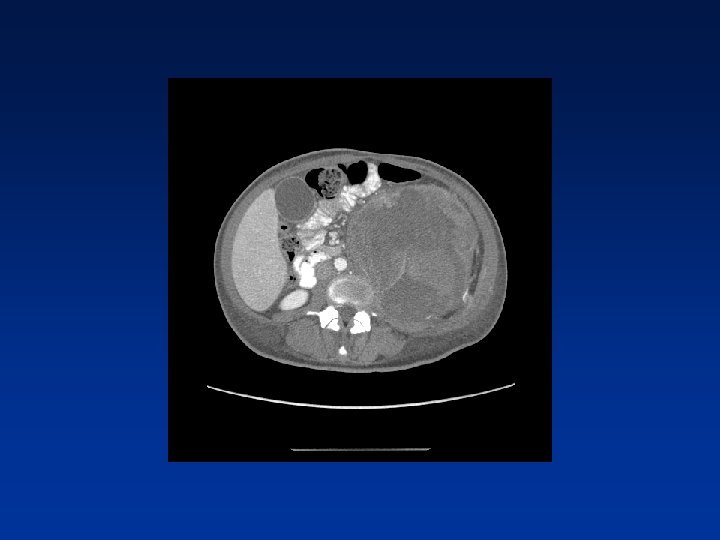

CASE